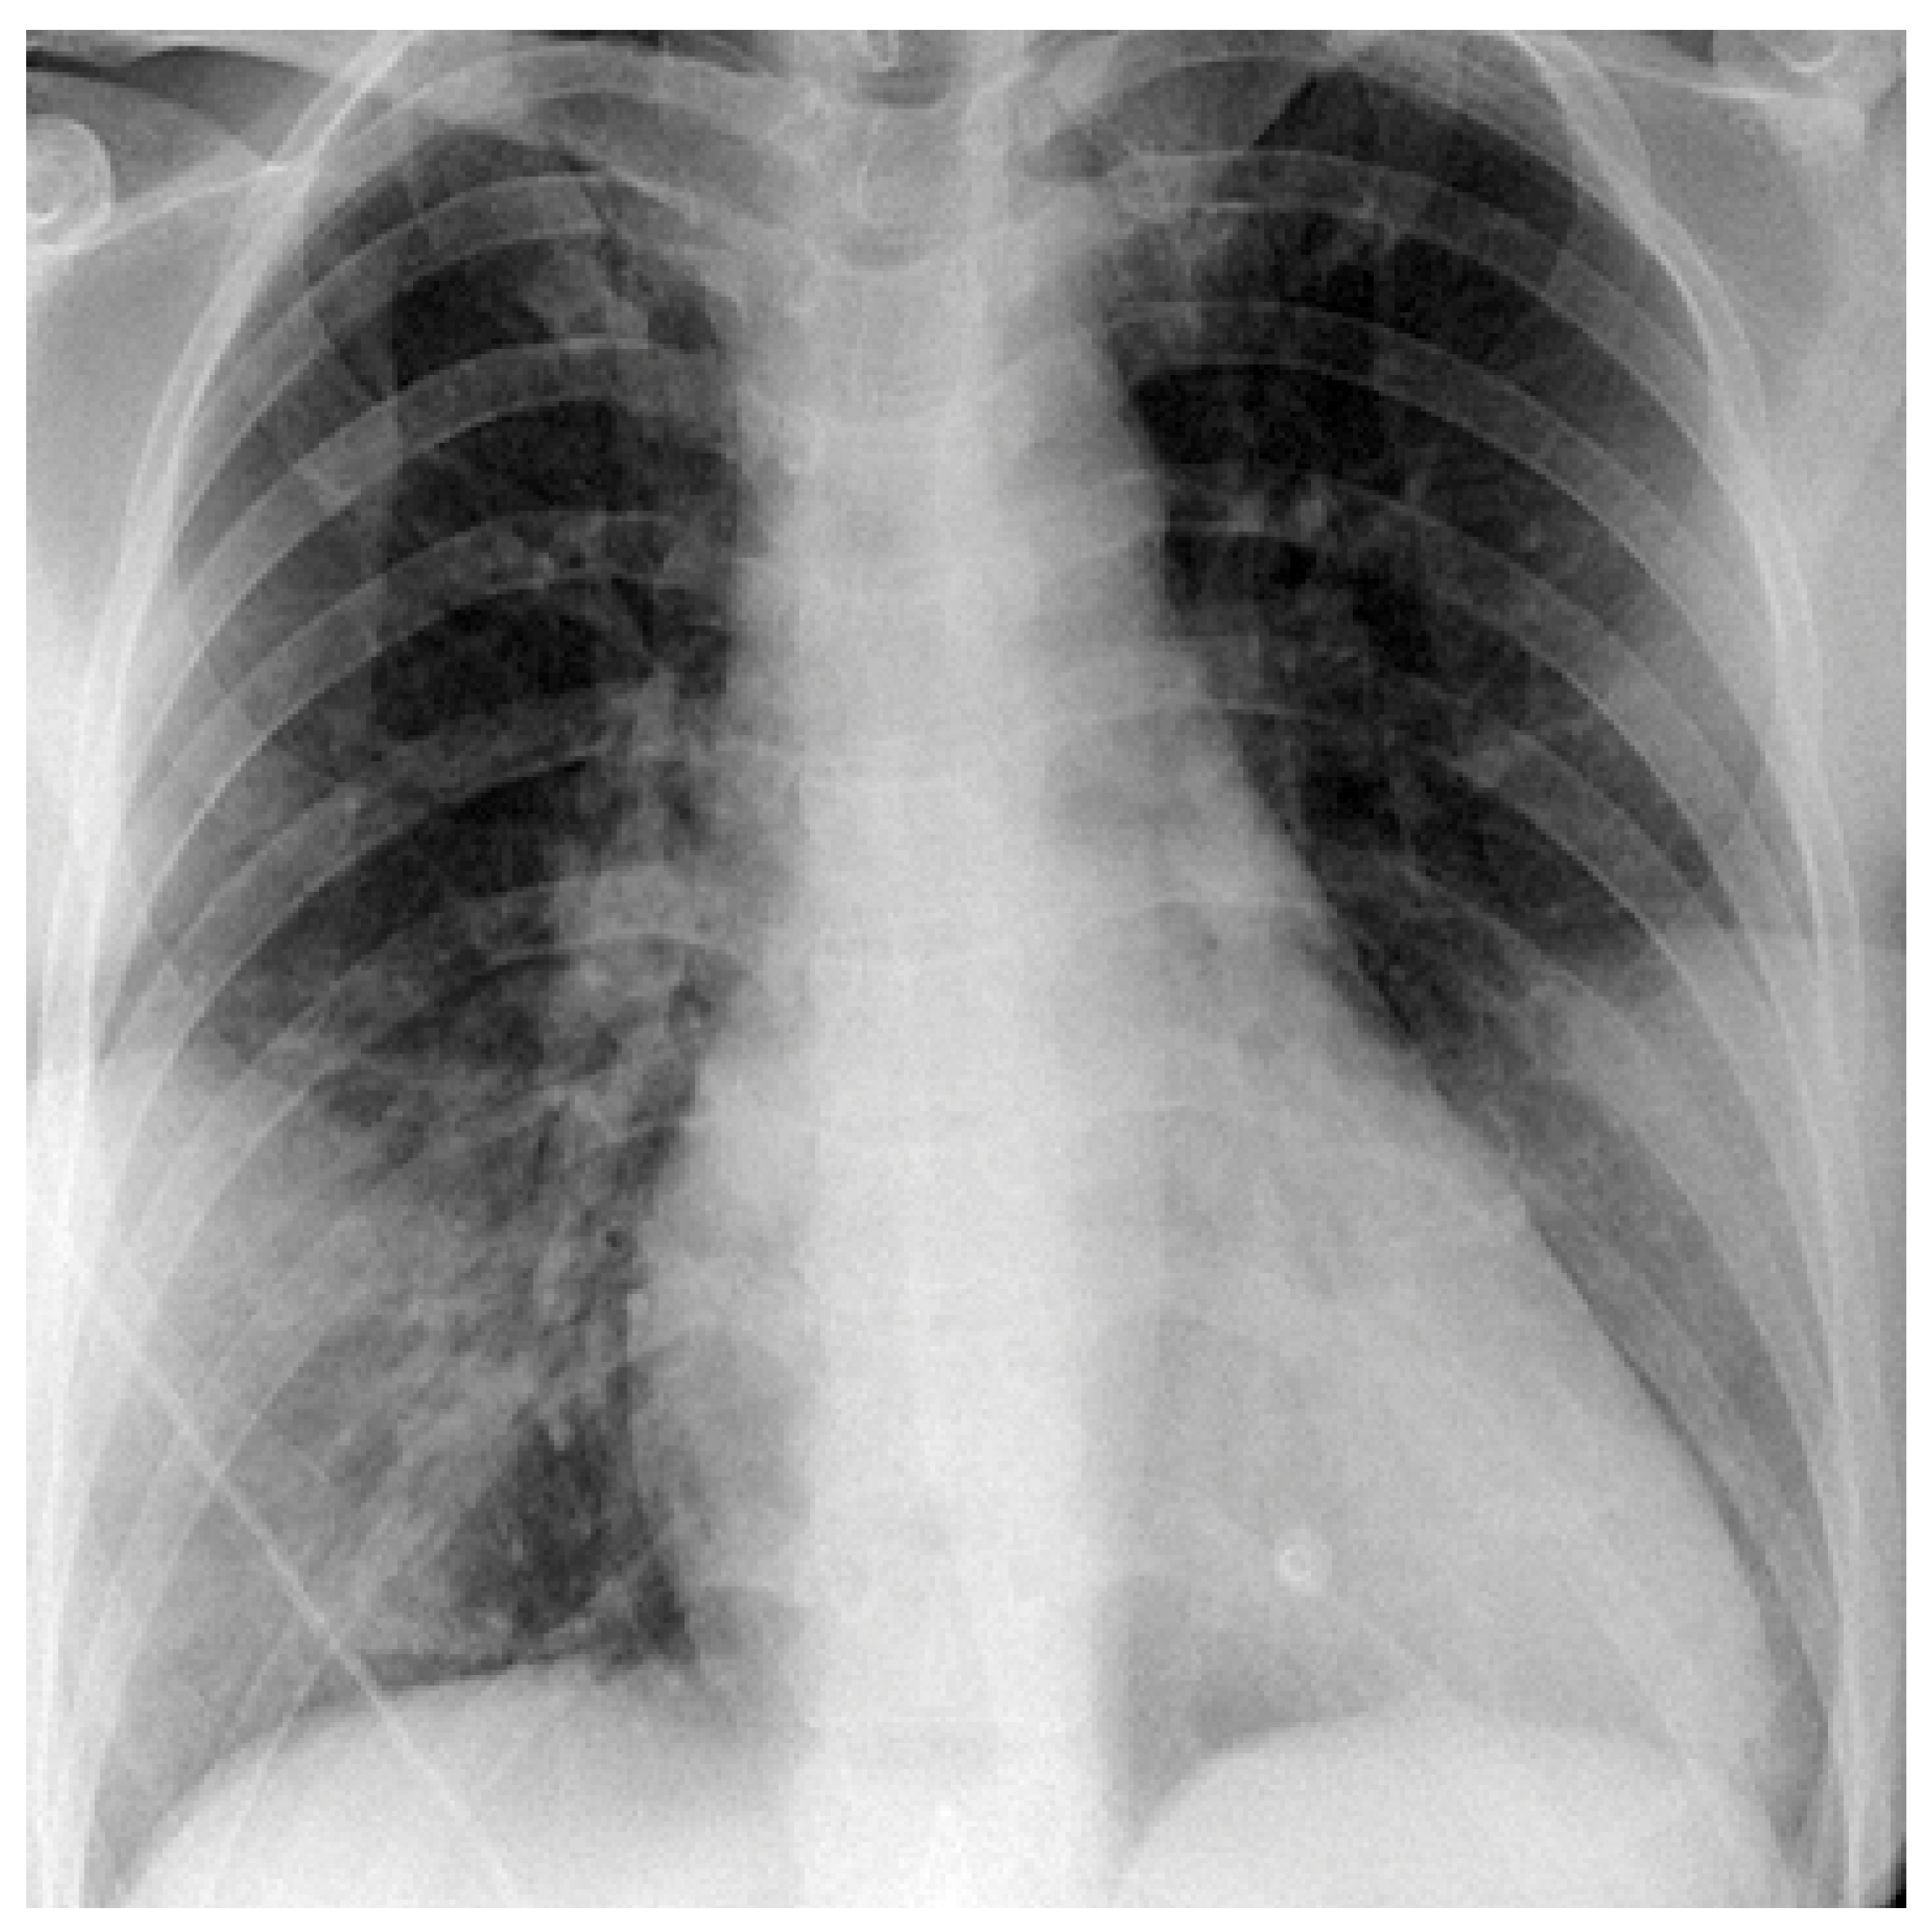

Case 2

Case 3